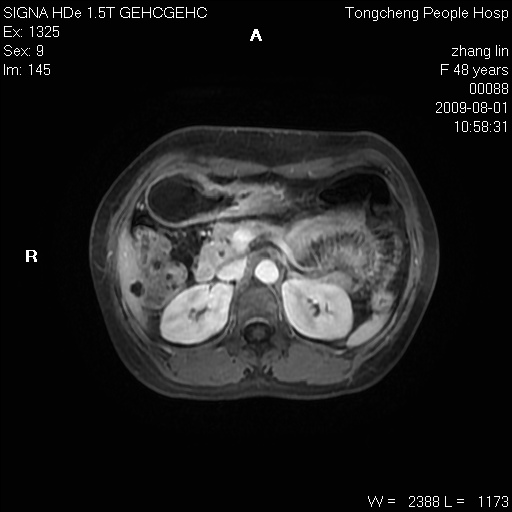

女,48岁。健康体检,彩超发现右肾占位性病变。平素健康。

临床诊断:右肾占位性病变,性质待定(囊肿?肿瘤?)。

上中腹部mr平扫+增强扫描,图像如下:

右肾上极见一类圆形病灶,t1wi呈等信号t2wi呈等高混杂信号,三期增强无强化,边界清---考虑囊肿出血。

同反相位均表现为等信号,病变无强化,考虑含蛋白的囊肿可能,弥散加权相或许有些帮助,